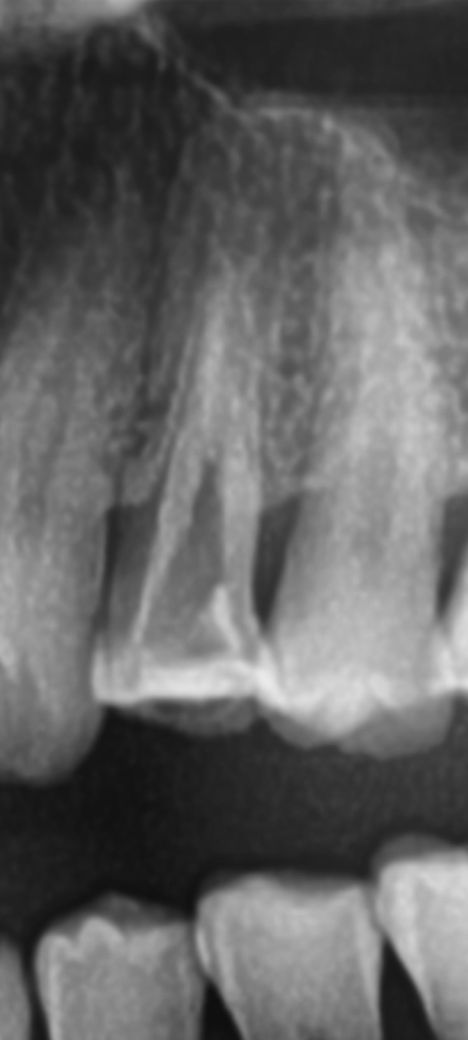

치아 균열이나 염증 소견있는지 한번 봐주세요

사진에 염증소견이나 치아 균열등이 있나요?

사진으로 봤을 경우에는 치질의 상실이 많이 된것으로 보입니다.

이런경우 충치가 치조골에 내려가 있거나 파절선이 있을수 있습니다.

치아의 균열은 엑스레이 상으로 보일정도면 치아를 발치해야될 상태입니다. 치아 뿌리끝에 금이 간게 아닐까 생각됩니다.

만약 있다면 발치해야 할까요? -> 엑스레이상 명확히 크랙이나 염증이 보이진 않습니다 여러번 신경치료를 진행해도 차도가 없으면 빼야합니다